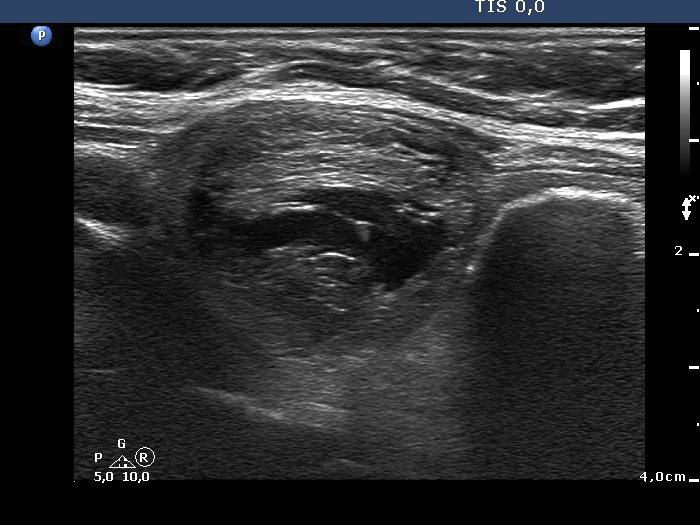

Benign cystic lesion (cytological diagnosis) - case 28

The hyperechogenic lines in the dorsal wall of the cystic area do not cause concern (arrows), while the granules (arrowheads) might do.